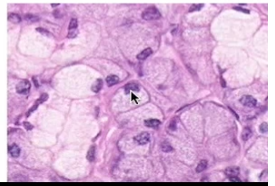

Name this cell type and where it would predominate

Serous cells

Parotid and submandibular glands

(Dark staining cells + round nuclei)